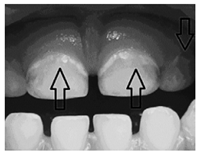

Manchas brancas ativas são consideradas lesões iniciais

cariosas e são frequentemente encontradas em dentes

decíduos. Visando a preservação da estrutura dentária em

odontopediatria, um material dentário pode ser

adequadamente usado com a finalidade de remineralizar a

estrutura descalcificada. Qual material seria este?